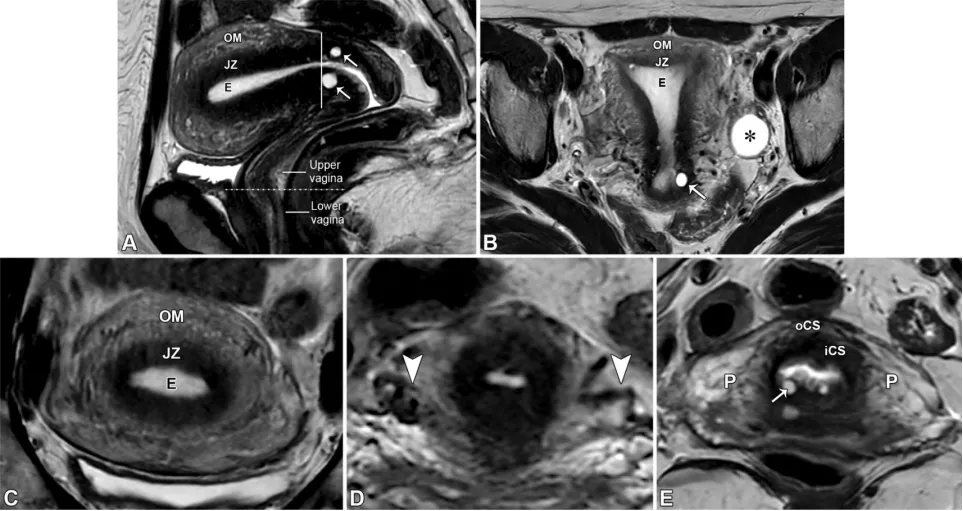

图2展示了女性盆腔MRI评估中常用的成像平面。经子宫的正中矢状面插图(A)显示了关键的MRI平面定位。A中的红线与子宫体平行,指示冠状斜位或卵巢轴的定位(如B中红线框所示),这有助于区分附件肿块的子宫起源和卵巢起源,并勾勒出子宫底的外轮廓,这在评估苗勒管畸形时具有重要意义。A中的黄线与子宫体垂直,显示子宫轴位斜平面的定位(如C中黄线框所示)。该平面用于评估子宫内膜癌分期中的肌层浸润深度,或显示子宫平滑肌瘤的位置。A中的灰线与宫颈垂直,代表宫颈轴位斜平面的定位(如D中灰线框所示),这对评估宫颈癌分期中的宫旁浸润至关重要。最后,A中位于膀胱颈水平的蓝色虚线将阴道分为上三分之二和下三分之一,这一区分对宫颈癌分期很重要。E=子宫内膜,iCS=宫颈内基质,JZ=交界区(子宫内肌层),oCS=宫颈外基质,OM=子宫外肌层,P=宫旁组织。图3,一名46岁女性患者在T2加权图像上子宫体和宫颈的正常表现。矢状位(A)、斜冠状位(B)、子宫斜轴位(C)、峡部斜轴位(D)和宫颈斜轴位(E)图像显示了子宫和宫颈的正常分区解剖结构。如A-C所示,位于中央的高信号子宫内膜(E)被低信号的结合带(JZ,即子宫内肌层)和中等信号强度的子宫外肌层(OM)所环绕。峡部标志着子宫颈连接处以及内口的位置,其特征为子宫外部轮廓变窄、宫颈管在通入子宫内膜腔之前呈漏斗状(A),以及子宫血管的入口(D中的箭头)。在矢状位T2加权图像(A)上,水平放置于膀胱颈的虚线将阴道的上三分之二与下三分之一区分开来,这一区分与宫颈癌分期相关。注意宫颈内的小纳博特囊肿(A、B和E中的箭头),以及左卵巢内的T2高信号卵泡(B中的*)。iCS=宫颈内间质,oCS=宫颈外间质,P=宫旁组织。教学要点:磁共振成像(MRI)能提供卓越的解剖学细节,多平面T2加权成像则是解剖学评估的基础。放射科医生必须透彻理解女性骨盆解剖结构,才能有效解读盆腔MRI。- 腹膜外间隙内有器官、肠系膜和结缔组织。腹腔内器官完全被腹膜包裹,而腹膜外器官则位于腹膜外间隙(图4)。

卵巢——卵巢是可活动的腹膜内器官,由卵巢韧带(连接卵巢与子宫角)、卵巢系膜(将卵巢固定于阔韧带)和悬韧带(连接卵巢与盆腔侧壁并包裹性腺血管)支撑(图6)(36)。性腺动脉起源于肾动脉下方的腹主动脉;右侧性腺静脉汇入下腔静脉,左侧性腺静脉汇入左肾静脉。性腺静脉直径大于0.8厘米为异常,尽管性腺静脉直径与静脉反流之间的相关性较差(37)。性腺血管走行于腰大肌前方、输尿管外侧。 卵巢的表现随月经周期阶段和绝经状态而变化。绝经前卵巢为较大的椭圆形结构,在T2加权成像上能清晰显示分区解剖结构,包括T2低信号的皮质、T2等信号的髓质(含疏松排列的基质和血管)、T2高信号的薄壁卵泡,偶尔可见黄体(19,38)。黄体因有黄素化的卵泡膜细胞而呈现T2等信号的厚壁,在退化过程中会变得锯齿状。非出血性黄体中央呈T1低信号、T2高信号,而出血性黄体中央呈T1和T2高信号,有时可见血细胞比容平面。静脉注射对比剂后,卵巢皮质和基质轻度强化,强化程度低于子宫肌层,而黄体壁则表现为早期明显强化(38)。绝经后卵巢比绝经前卵巢小,皮质和髓质呈T2等信号至低信号,偶尔可见小囊肿(38)。表S2以及图7-10详细描述了常见的生理性和其他良性卵巢表现的MRI特征(19,38-42)。图7. 两位不同患者的正常经前卵巢,突出显示了生理学观察结果。(A)示意图显示了带有卵泡的经前卵巢。(B)一位27岁女性患者的轴位T2加权图像显示一个椭圆形卵巢,具有T2低信号皮质(箭头)、T2等信号髓质(白色*)和多个T2高信号卵泡(黑色*)。(C、D)一位30岁女性患者的轴位T2加权(C)和对比增强脂肪抑制T1加权(D)图像显示了黄体(CL),这是经前女性常见的生理学表现。其影像学表现随发育阶段而变化。典型的黄体在T2加权成像上表现为囊性结构,中心呈高信号,壁厚且呈锯齿状,信号强度中等(C中的箭头),在静脉注射造影剂后明显强化(D中的箭头)。图8. 一名34岁闭经女性患者的多囊卵巢综合征与继发性非典型子宫内膜增生。(A)示意图展示了多囊卵巢,这是一种常见的内分泌疾病,影响高达10%的育龄女性。多囊卵巢综合征的诊断依据Rotterdam标准,该标准要求满足以下三项中的至少两项:多囊卵巢、月经稀发或无排卵,以及高雄激素血症。多囊卵巢的定义为:至少一侧卵巢的体积达到10毫升或以上,或者每个卵巢有20个或更多的卵泡(详见表S2)。(B)轴位T2加权图像显示双侧多囊卵巢增大,中央为T2等信号基质(小*),周围有多个T2高信号卵泡。(C)矢状位T2加权图像显示子宫内膜腔内呈不均匀的T2等信号(大*),对应活检证实的非典型子宫内膜增生。在所有增强后序列(包括延迟图像,未显示)中,非典型子宫内膜增生的强化程度低于子宫肌层,这与子宫内膜癌的强化模式相似。图9. 一名27岁女性患者的右侧卵巢扭转,该患者表现为急性盆腔疼痛。轴位T2加权图像显示右侧卵巢(RO)增大且水肿,伴有外周卵泡(箭头所示)。与正常的左侧卵巢(*)相比,右侧卵巢位置异常,位于子宫(U)的中央后方。卵巢扭转的其他表现(未显示)可能包括血管蒂扭转以及强化程度不一,这取决于缺血程度或是否存在梗死。图10. 一位43岁女性患者的输卵管卵巢脓肿,该患者在子宫内膜活检后出现恶心、呕吐和盆腔疼痛症状。轴位T2加权像(A)和对比增强脂肪抑制T1加权像(B)显示左侧附件区有一个多房囊性肿块。该肿块内含有脓性液体,在T2加权像上表现为不同的信号强度(A中的*),并具有增厚的强化壁以及多个强化分隔(B中的箭头)。高b值扩散加权像和ADC图(未显示)显示扩散受限,与脓液的存在相符。经皮引流后获得的细菌培养结果显示大肠杆菌阳性。——输卵管从子宫角延伸至卵巢(39)。近端的壁内部分穿过子宫肌层;远端带有伞端的漏斗部开口于卵巢附近的腹膜腔。输卵管被阔韧带的输卵管系膜包绕(图6)。在MRI上,它们表现为卵巢和子宫之间的T2低信号管状结构。子宫体和宫颈解剖。——子宫由子宫体和宫颈组成,宫颈下段(或子宫颈外口部)突入阴道上部(图2、3)(24、25、43)。在T2加权成像上,绝经前子宫的子宫体(子宫内膜、结合带和外肌层)和宫颈(宫颈管、宫颈内间质和宫颈外间质)均显示出清晰的分区解剖结构。绝经后或接受放射治疗后,这种分区解剖结构会变得不清晰(24、25、43)。子宫内膜腔由均匀的T2高信号子宫内膜衬里,延伸至同样为T2高信号的宫颈管(38)。子宫内膜厚度在子宫矢状面中部沿子宫长轴测量,其数值会随绝经状态和月经周期阶段而变化(表S3)(38、44-49)。对于有绝经后出血的患者,子宫内膜厚度≥5mm为异常;而无症状患者的阈值则不太明确(50)。结合带(子宫内肌层)呈T2低信号,向尾侧延续为T2低信号的宫颈内纤维间质。子宫外肌层呈T2等信号,过渡为宫颈外间质的T2等信号。正常结合带厚度≤8mm,若无微囊肿则可达11mm(45)。 子宫峡部是子宫体与宫颈之间的过渡区,在矢状位T2加权成像上表现为局限性缩窄,在轴位斜向T2加权成像上可见子宫血管进入(图2、3)(24、25)。宫颈内口和外口分别是宫颈管的上下开口。宫颈围绕宫颈管,包括上皮衬里和宫颈间质(43)。宫颈上段由腺状柱状上皮覆盖,宫颈下段(包括子宫颈外口部)由鳞状上皮覆盖。鳞状上皮与柱状上皮的交界处(鳞柱交界)在生育年龄具有动态变化,是大多数宫颈癌前病变和宫颈癌的起源部位。宫旁组织由主韧带和宫骶韧带构成,从宫颈两侧延伸至盆侧壁,包绕子宫血管、神经和输尿管(图2、3)。表S3以及图11-13概述了常见的子宫体和宫颈良性病变的MRI特征(38、44-49)。图11. 一位50岁女性患者的子宫内膜息肉,该患者在乳腺癌切除术后接受他莫昔芬治疗。(A)子宫矢状面示意图显示息肉状子宫内膜病变,伴有因子宫内膜腺体扩张而形成的囊性病灶。(B)冠状斜位T2加权像显示子宫内膜内有一个带蒂病变,具有T2低信号的纤维血管核心(白色箭头)和T2高信号病灶(黑色箭头),这些表现提示为子宫内膜息肉。通常可见明显的强化,与子宫肌层的强化程度相似(未显示)。明确诊断需要宫腔镜下切除,因为子宫内膜息肉、增生和肿瘤可能同时存在,且在影像学特征上可能重叠。偶然可见子宫腺肌症,表现为结合带内存在微囊肿(箭头所示)。图12. 弥漫性和局灶性子宫腺肌病(或子宫腺肌瘤)。(A)子宫矢状面中部的插图显示了弥漫性子宫腺肌病(上图)与局灶性子宫腺肌病或子宫腺肌瘤(下图)的对比。(B、C)两名不同的月经过多患者的矢状位T2加权图像显示,T2低信号的交界区(JZ)弥漫性增厚,伴有散在的T2高信号微囊肿(B中的实线),以及前部交界区伴有微囊肿的局灶性肿块样不对称增厚(C中的虚线)。这些表现是由于子宫肌层内存在异位子宫内膜腺体和间质(微囊肿)以及反应性平滑肌增生(交界区增厚)所致。图13. 纳博特囊肿与隧道簇。插图(A)及两名不同患者的子宫正中矢状面T2加权图像(B、C)显示,浅层宫颈基质内的单房囊肿为典型的纳博特囊肿(A图左图;B图),而向宫颈基质深部延伸的多房囊肿为隧道簇的特征性表现(A图右图;C图)。务必在增强图像上排除强化实性组织的存在(未显示),因为多房性宫颈病变中若出现强化实性组织,应怀疑宫颈胃型腺癌。可能需要进行宫颈锥形活检以明确诊断。子宫在骨盆内的位置会因膀胱充盈程度和盆腔瘢痕情况而有所不同。倾位指的是宫颈与阴道之间的角度:前倾位是向前倾斜,后倾位是向后倾斜(图14)(38)。屈曲描述的是子宫体与宫颈之间的角度:前屈是向前弯曲,后屈是向后弯曲(38)。图14. 插图(A)和磁共振图像(B、C)显示了女性骨盆内子宫的各种位置。子宫倾(Version)指的是宫颈与阴道之间的角度:A中的上组插图将该角度显示为黄线相对于红线的倾斜度。前倾(Anteversion)指向前倾斜,后倾(Retroversion)指向后倾斜。子宫屈(Flexion)描述的是子宫体与宫颈之间的角度:A中的下组插图将该角度显示为蓝线相对于黄线的倾斜度。前屈(Anteflexion)指向前弯曲,后屈(Retroflexion)指向后弯曲。两名患者的矢状位T2加权图像(B、C)中,B显示的是前倾前屈位子宫,C显示的是后倾后屈位子宫。阴道是一个纤维肌性结构,通过膀胱阴道隔与膀胱相隔,通过直肠阴道隔与直肠相隔(图4)(51)。在轴位T2加权成像上,绝经前阴道通常呈H形或W形塌陷,具有高信号的黏膜皱襞和低信号的壁。绝经后,皱襞消失,阴道壁厚度变薄。阴道上部有由突出的宫颈形成的穹窿,阴道下部通过阴道口开口于外阴前庭。表S4和图15详细描述了常见良性阴道病变的MRI特征(51-53)。图15. 四个不同患者的矢状面示意图(A)和轴位T2加权图像(B–E)显示了阴道囊肿、斯基恩氏腺囊肿以及尿道憩室。巴氏腺囊肿:位于耻骨联合处或其下方阴道后外侧壁的单房囊肿(A中的灰色椭圆形,B中的T2高信号囊性病变)。加特纳管囊肿:位于耻骨联合处或其上方阴道前外侧壁的单房囊肿(A中的蓝色椭圆形,C中的T2高信号囊性病变)。斯基恩氏腺囊肿:位于耻骨联合下方、阴道前方、尿道下段外侧的单侧或双侧小单房囊肿(A中的浅黄色椭圆形,D中的T2高信号囊性病变)。尿道憩室:在耻骨联合附近,尿道中远端后外侧出现的圆形、椭圆形或U形T2高信号液性囊袋状突起(A中的尿道囊袋状突起)。在罕见情况下,尿道憩室可能完全环绕尿道(E中的T2高信号环形囊性病变)。外阴由女性外生殖器组成(图16)(53)。阴阜位于耻骨联合前方,由脂肪组织构成。大阴唇是位于阴阜下方并与其相连的厚皮肤皱襞。小阴唇是大阴唇之间较薄的皱襞,向前会合于阴蒂头。小阴唇之间的前庭包含尿道外口(尿道口)和阴道口(阴道开口)。图16. 示意图(A)和轴位T2加权图像(B)显示了外阴区域或女性外生殖器。阴阜位于耻骨联合前方,由脂肪组织构成。大阴唇是位于阴阜下方且与其相连的厚皮肤皱襞。小阴唇是大阴唇之间较薄的皱襞,向前汇聚于阴蒂头。小阴唇之间的前庭前部有尿道外口(尿道口),后部有阴道口(阴道开口)。参考文献:https://doi.org/10.1148/rg.250029